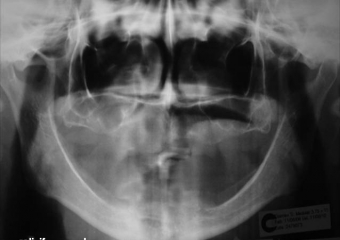

Raio X inicial